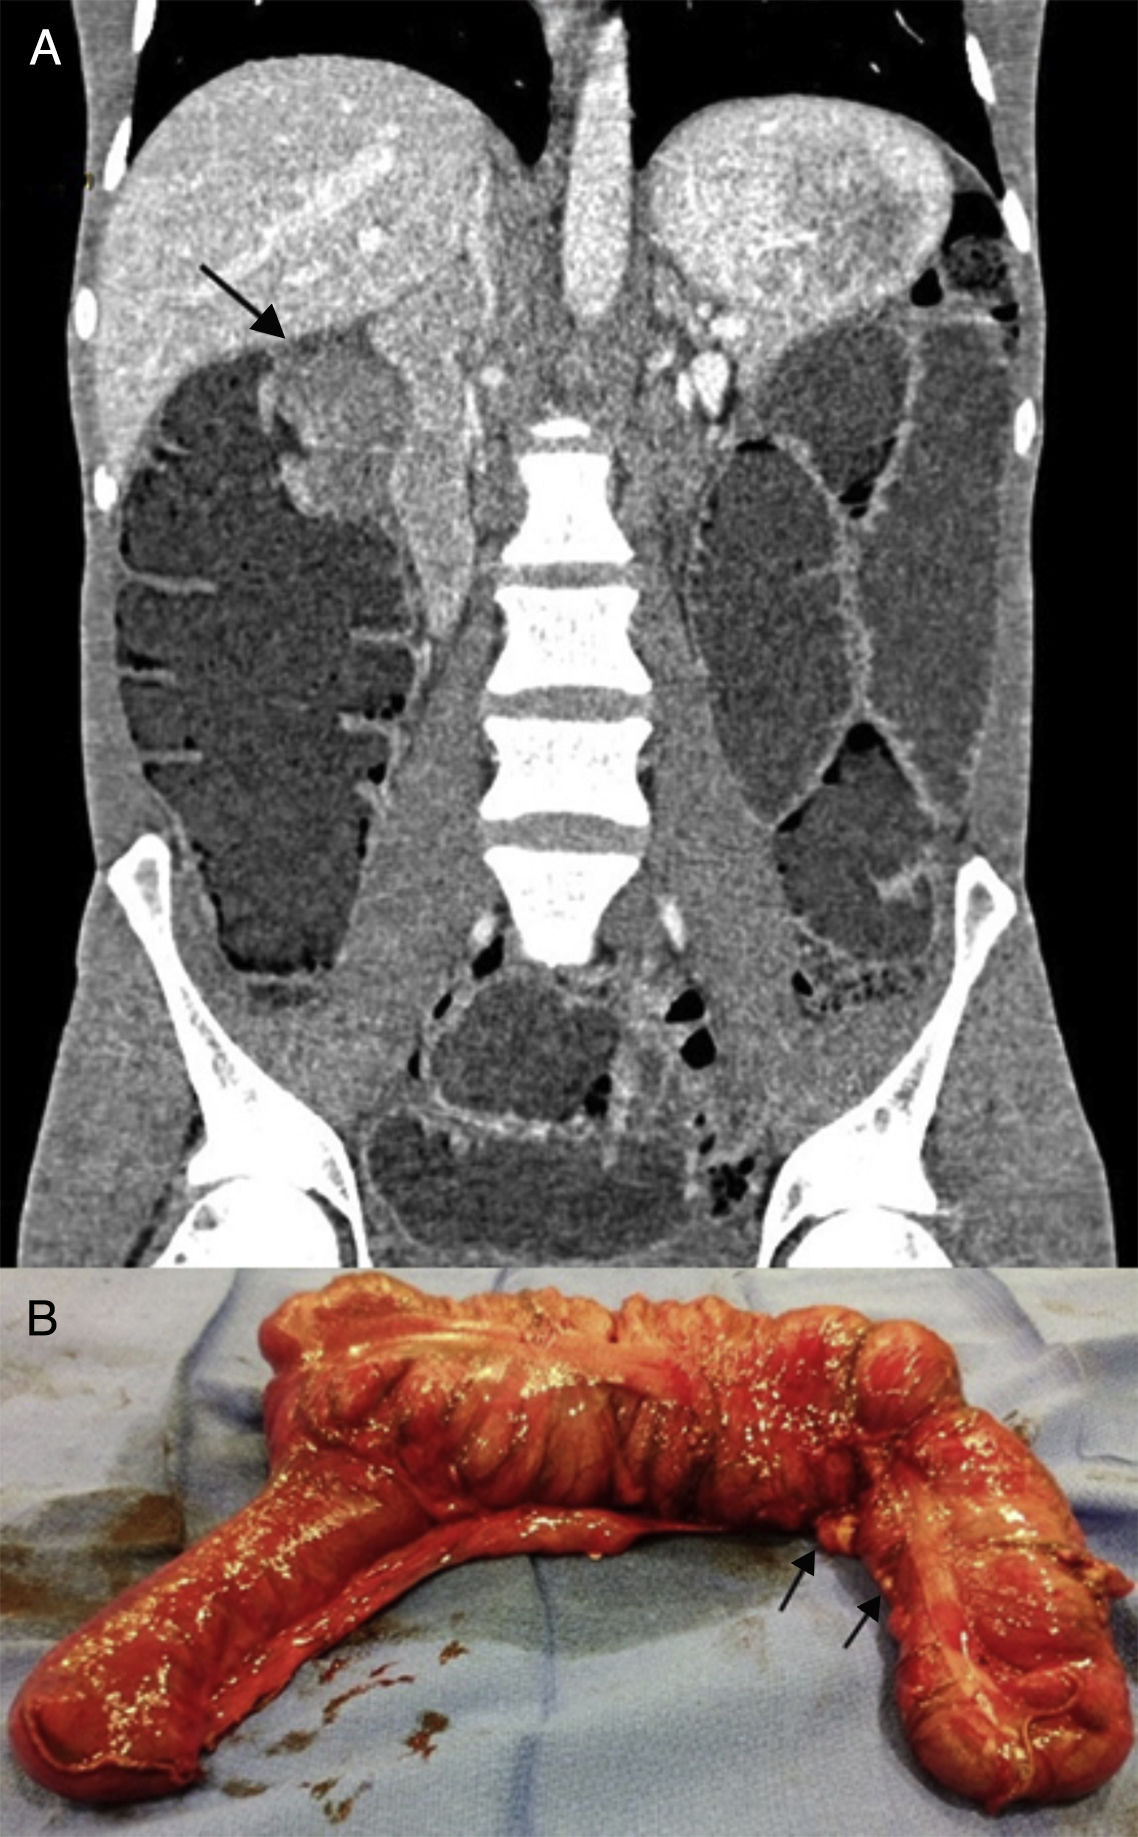

The second case was a 38-year-old man with no family history of colon cancer. He was recently diagnosed as seropositive for human immunodeficiency virus, stage A1, with a viral load of 120000 copies/ml. He presented with asthenia and 10-day progression of abdominal pain, nausea, vomiting, absence of bowel transit, and great abdominal distension. Plain x-ray showed marked small bowel dilation. Emergency CT scan identified an irregular 6 x 6cm mass at the level of the hepatic angle (fig. 2A) with proximal cecal dilation up to 6.2cm, along with multiple retroperitoneal lymph node conglomerates and millimetric hypodense lesions in the liver parenchyma. Emergency right hemicolectomy was performed, with the intraoperative finding of diffuse intestinal carcinomatosis (fig. 2B), mesenteric implants, and numerous hepatic lesions suggestive of metastasis.

The anatomopathologic diagnosis was poorly differentiated adenocarcinoma of the colon with > 50% signet ring cells, multiple metastatic peritoneal implants, lymph node conglomerates, and stage T4aN2bM1b. Immunohistochemistry showed microsatellite instability in the PMS-2 and MLH-1 genes and mutated K-ras gene.

The oncologic extension study revealed mediastinal adenopathies infiltrated with signet ring cell adenocarcinoma. Palliative chemotherapy was decided upon.